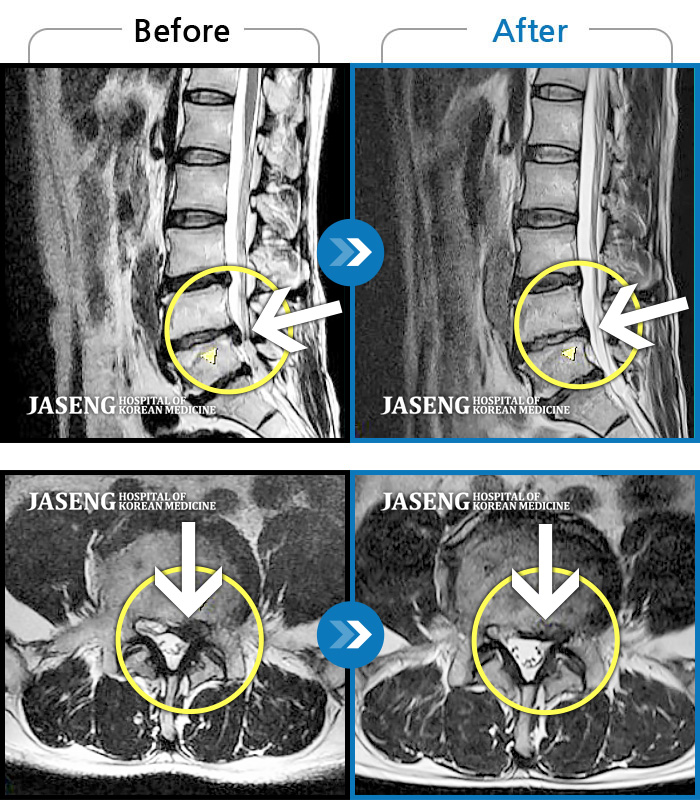

허리디스크

도움받은 사례

광주 · 장영우 원장

양측 허리의 묵직한 통증 및 기침 시 증상이 심화되어 내원하셨습니다.

촬영시기

2024.12.09 ~ 2025.05.24

2025.06.05